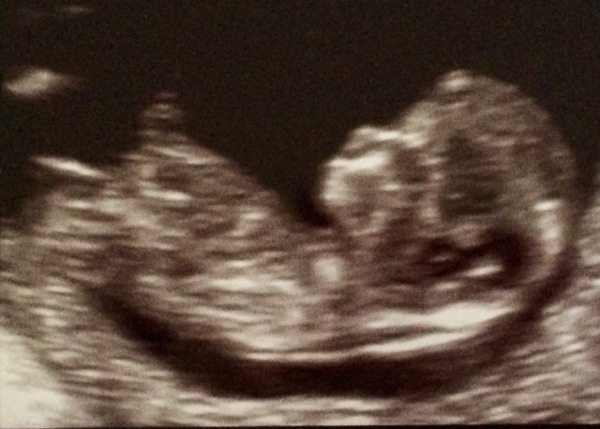

All is good. Scan went very well and baby is absolutely fine. We could see his/her little heart beating away! I'm actually 11 weeks 2 days, which makes more sense. Can't wait to tell the family over the weekend!! Smile

Beautiful scan pic life!!

life gorgeous! How many weeks were you by lmp pre scan?

Hello everyone! I've been away on school camp all week so just catching up now! Thankfully sickness is definitely on its way out and didn't cause too much bother while I was away. Congrats to everyone with good scan news - life your picture is fab! It looks like a proper baby!